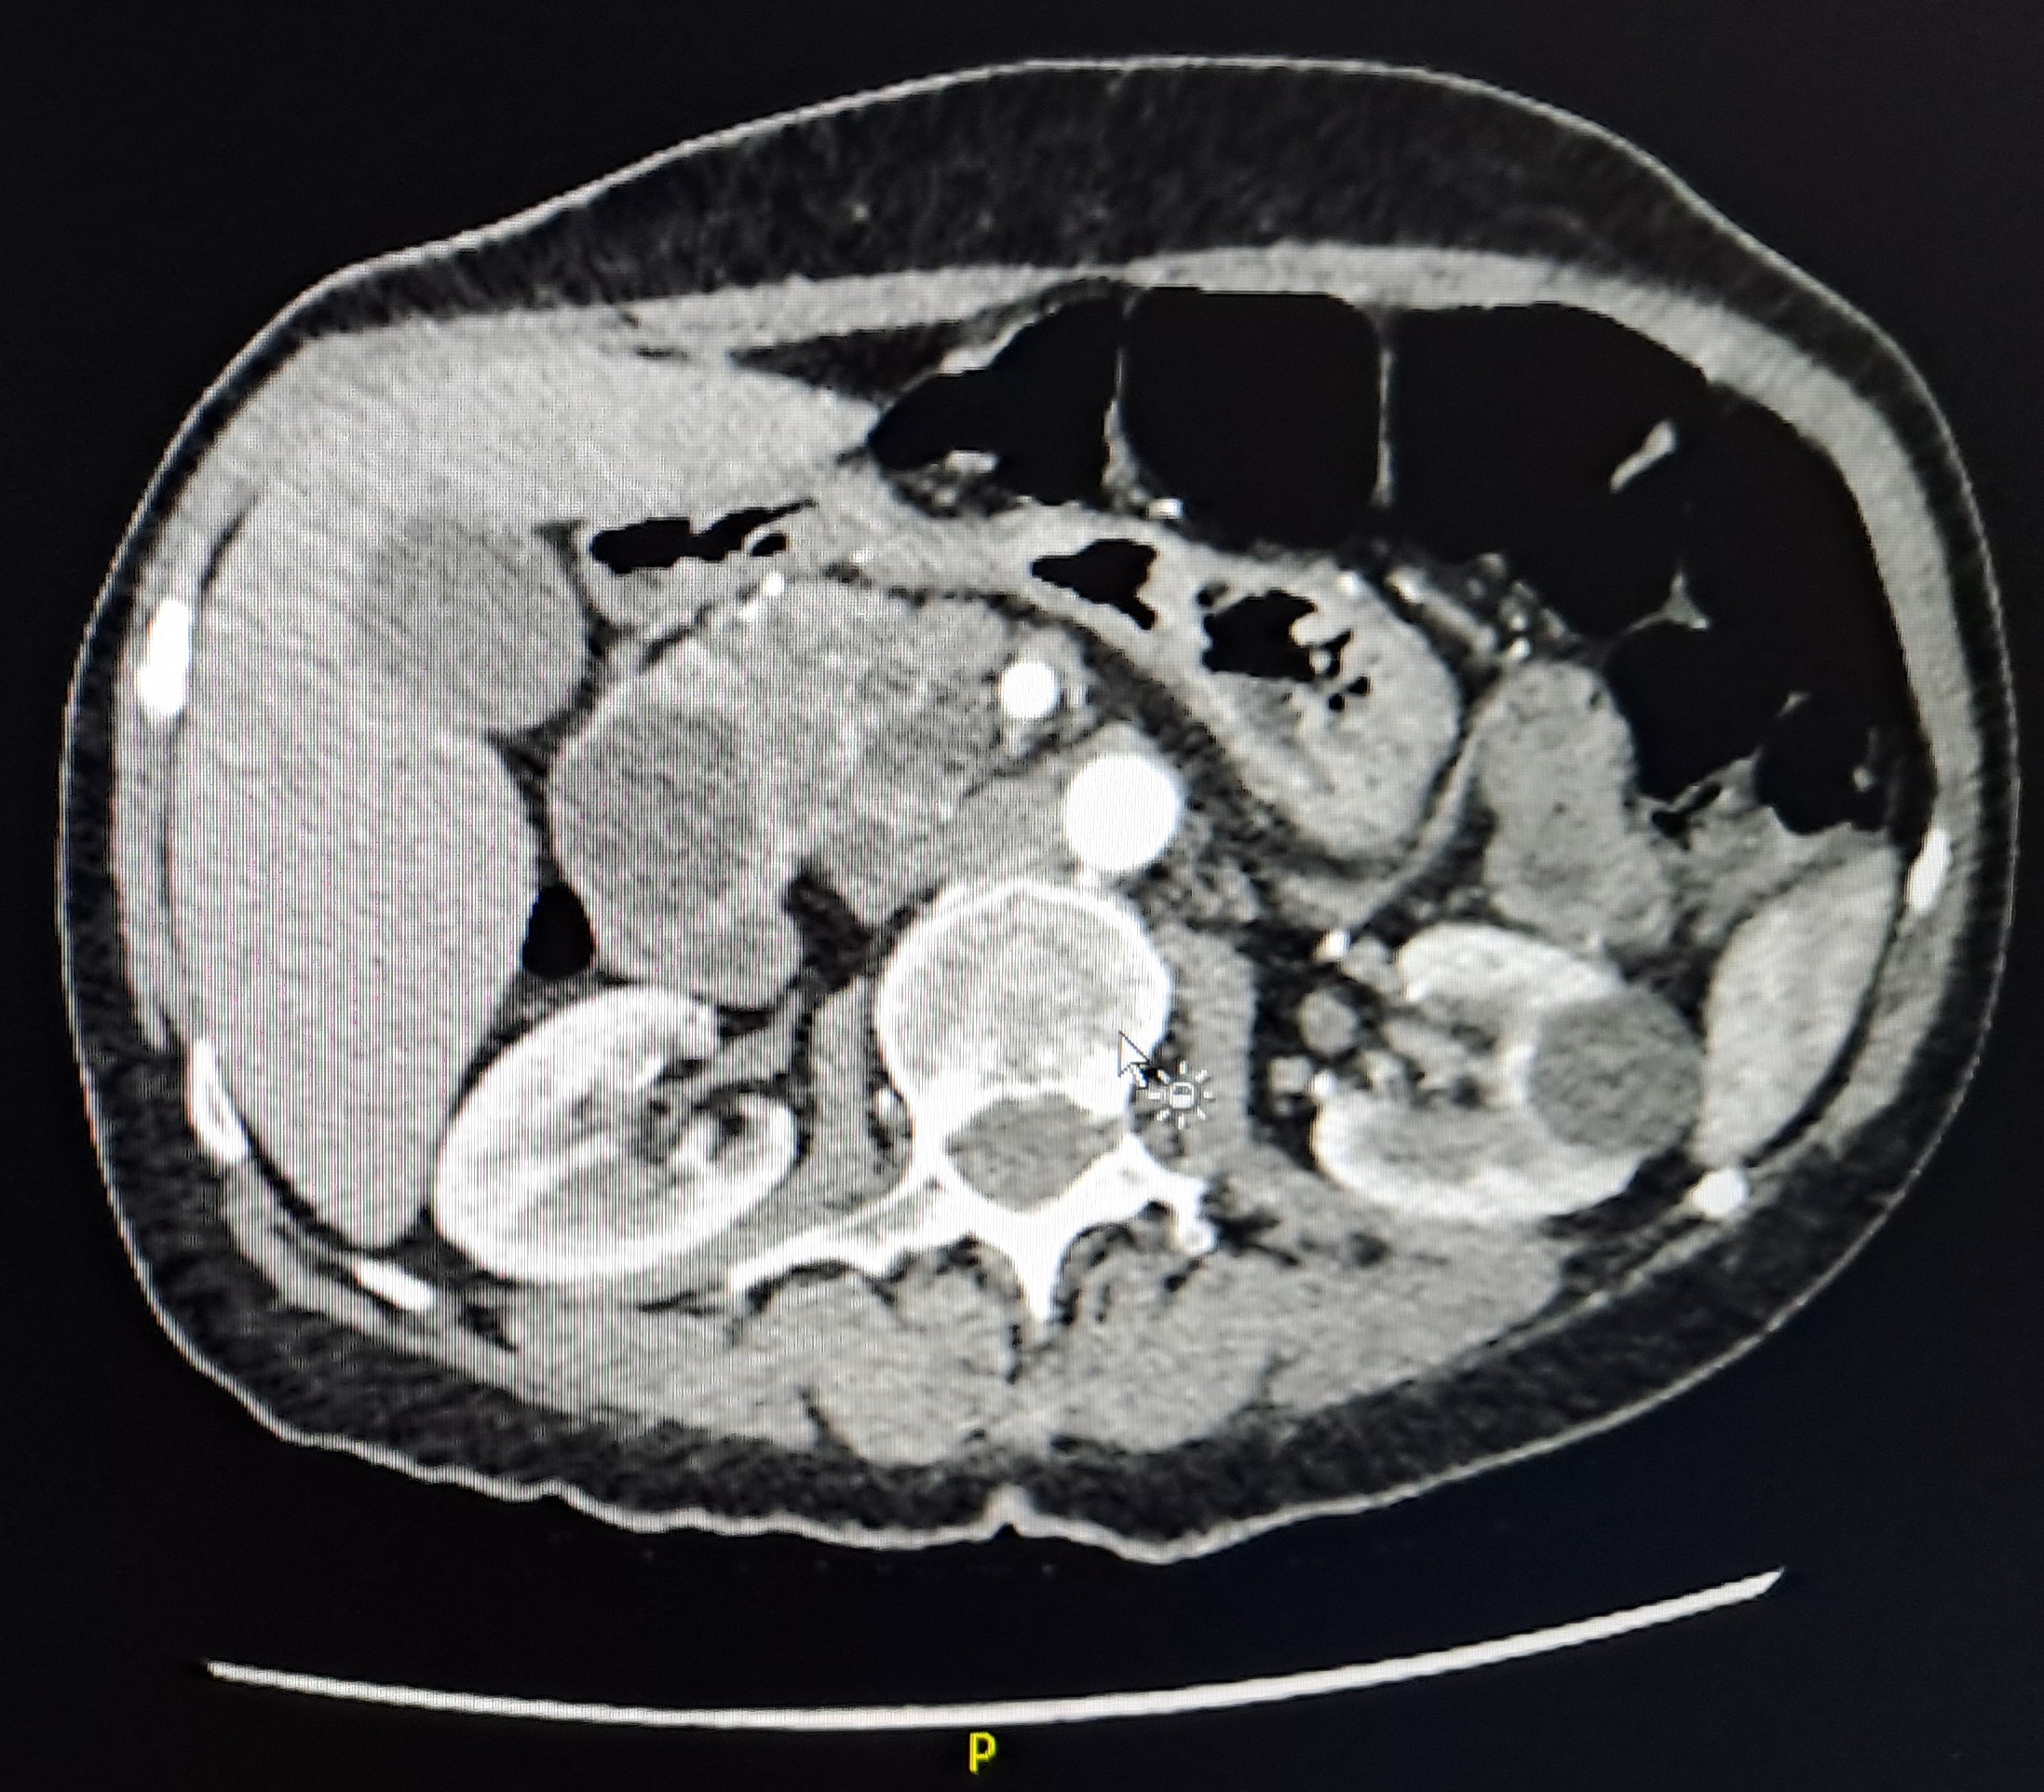

TAC abdominal: Probable neoplasia serosa quística en cabeza de páncreas de 6 cm, que condiciona compresión extrínseca sobre región bulboduodenal sin dilatación retrógrada.

Cistoadenoma seroso de cabeza de páncreas.